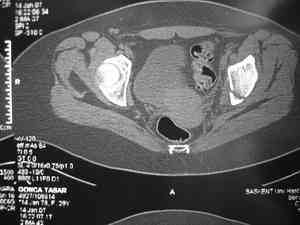

Dear group,30 years age female MVA front seat, head trauma + post column left acetabular fracture, 2.5 weeks skeletal traction. She is now conscious but still confused without any surgical treatment for brain edema.

Latest X rays and CAT is attached.Fracture within first 1.5 cm from the weight bearing dome, although AP and Obtrator oblique good, iliac oblique view reveals some displacement.I'm not sure that nonsurgical treatment will be OKHüseyin DemirorsBaskent UniversityDept of Orthopedics and TravmatologyAnkara TURKEY

My vote, given the amount of displacement on the iliac oblique and CT scan, would be for ORIF thru a posterior approach ASAP - these get pretty tough

I may get beat up for this, but I see very little displacement that concerns me on the CT. The radiograph is more concerning. I suspect it could look better, and the gap made smaller on CT. Not sure if it will affect outcome. I might give it a shot and try to see what could be done.